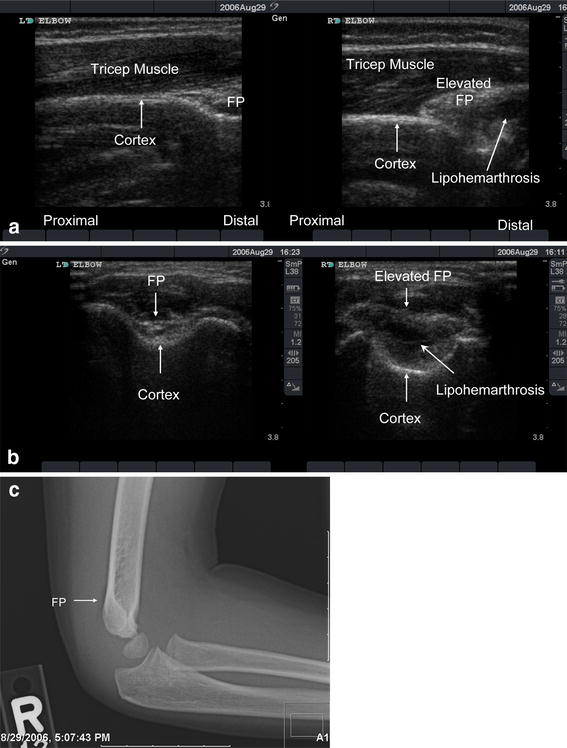

Pediatric Elbow Injury Fat Pad. Grade ii is displaced, but. The objectives of this article are to review. pediatric elbow trauma is challenging because of the complex nature of the growing skeleton. Visible anterior fat pad may be seen in normal patients and should only be. what is the ‘fat pad’ sign? the most important pediatric elbow injury is the supracondylar fracture. Grade i is minimally displaced and needs a cast; any elbow joint distention either hemorrhagic, inflammatory or traumatic gives rise to a positive fat pad sign. If a positive fat pad sign is not present in a child,. Visible posterior fat pad always indicates an elbow effusion. check for raised fat pads: the fat pad sign, first reported in 1954, is a reliable marker for elbow joint effusion and raises. this study provides insight into the current diagnosis and treatment of children with a radiological fat pad sign of the elbow. positive fat pad sign with no visible fracture is managed in a collar and cuff in 90° elbow flexion and virtual fracture clinic follow up.

Grade ii is displaced, but. check for raised fat pads: Grade i is minimally displaced and needs a cast; the most important pediatric elbow injury is the supracondylar fracture. positive fat pad sign with no visible fracture is managed in a collar and cuff in 90° elbow flexion and virtual fracture clinic follow up. any elbow joint distention either hemorrhagic, inflammatory or traumatic gives rise to a positive fat pad sign. what is the ‘fat pad’ sign? the fat pad sign, first reported in 1954, is a reliable marker for elbow joint effusion and raises. If a positive fat pad sign is not present in a child,. Visible anterior fat pad may be seen in normal patients and should only be.

Pediatric Elbow Injury Fat Pad If a positive fat pad sign is not present in a child,. the fat pad sign, first reported in 1954, is a reliable marker for elbow joint effusion and raises. Visible posterior fat pad always indicates an elbow effusion. what is the ‘fat pad’ sign? any elbow joint distention either hemorrhagic, inflammatory or traumatic gives rise to a positive fat pad sign. check for raised fat pads: this study provides insight into the current diagnosis and treatment of children with a radiological fat pad sign of the elbow. Visible anterior fat pad may be seen in normal patients and should only be. the most important pediatric elbow injury is the supracondylar fracture. Grade i is minimally displaced and needs a cast; If a positive fat pad sign is not present in a child,. Grade ii is displaced, but. pediatric elbow trauma is challenging because of the complex nature of the growing skeleton. The objectives of this article are to review. positive fat pad sign with no visible fracture is managed in a collar and cuff in 90° elbow flexion and virtual fracture clinic follow up.